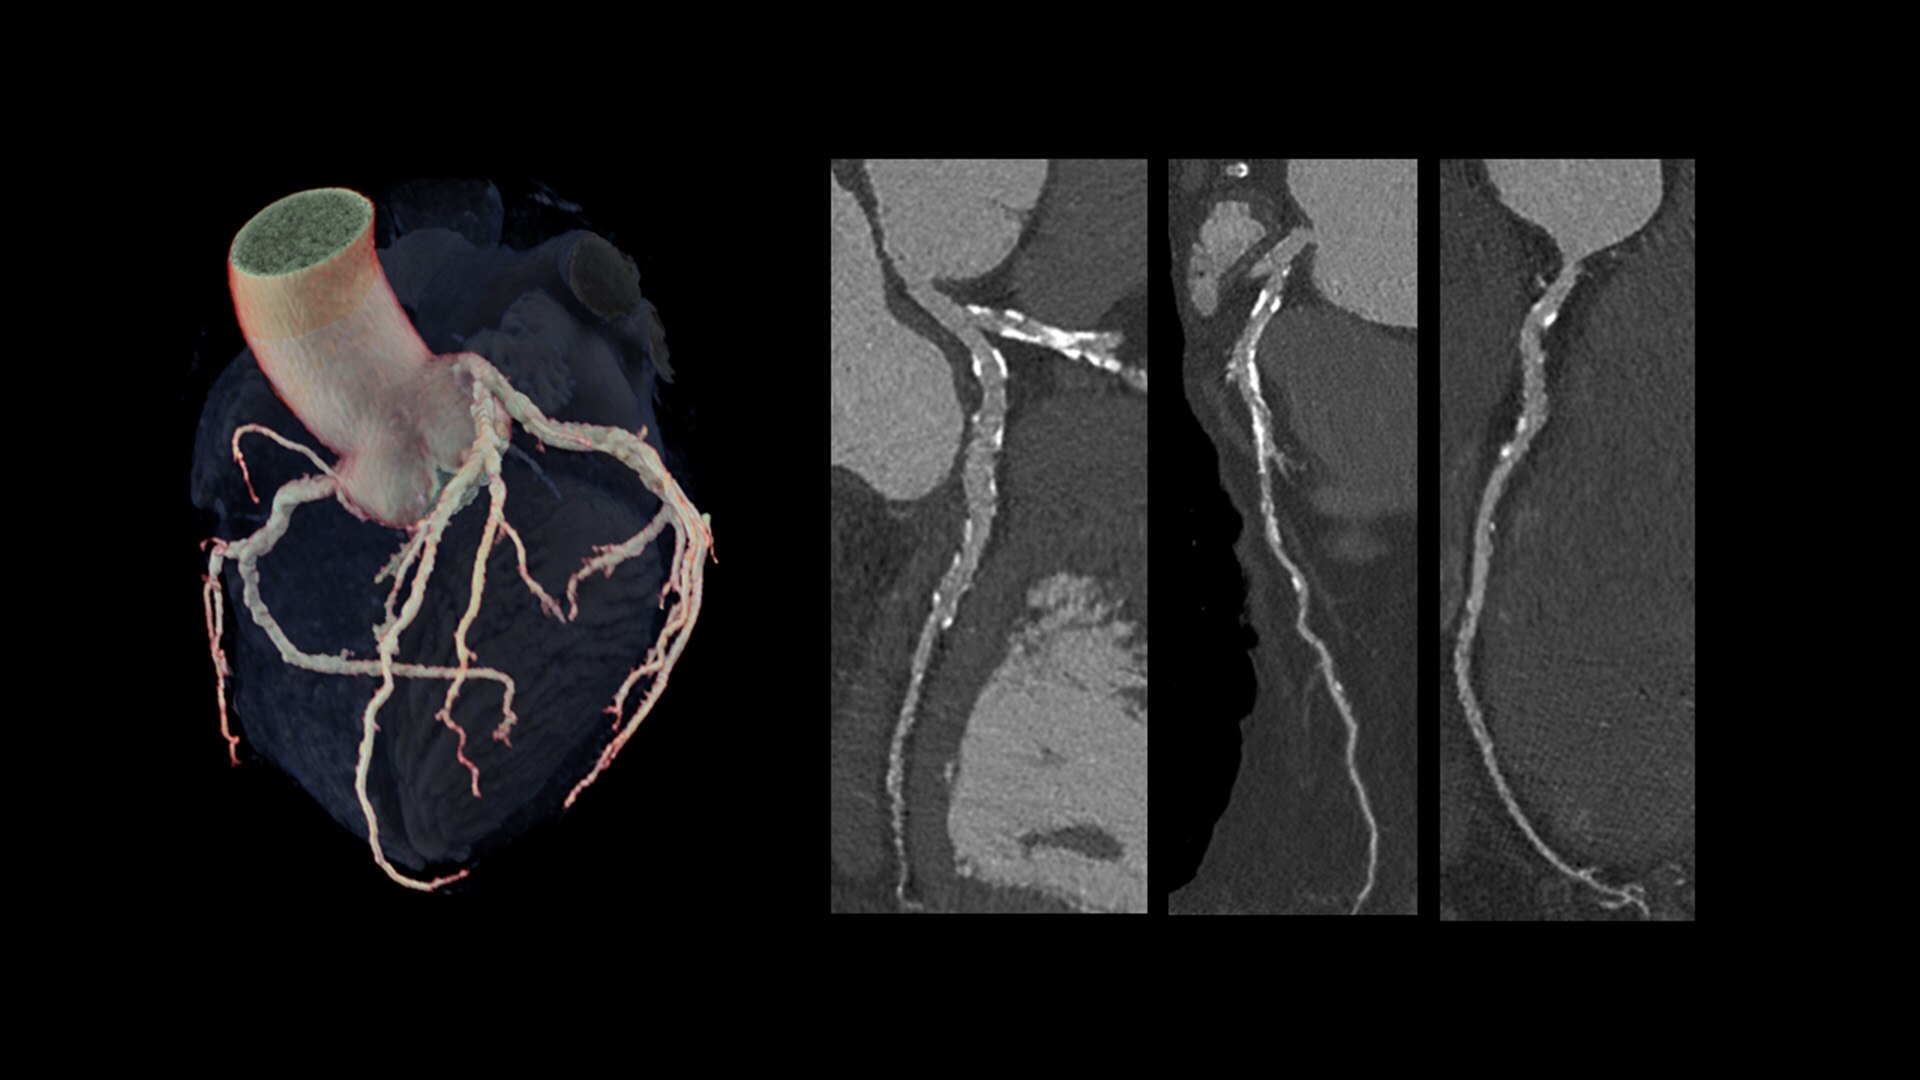

Cardiac CT has become a front-line, non-invasive imaging tool for diagnosing, treatment planning and monitoring of cardiovascular disease

Healthcare providers are striving to improve patient health but are struggling with increasingly complex exams, insufficient or inexperienced staff, and operational and capital efficiency. Revolution™ Vibe, designed to deliver leading-edge technology, features advanced cardiovascular capability. It improves patient access and operational efficiency, prioritizes patient care and supports your facility's growth with lower lifecycle costs.

Consistent, exceptional image quality for every patient

Unlimited 1-Beat Cardiac is designed to provide consistent, high-quality imaging for accurate diagnoses, even in challenging patients with atrial fibrillation, breath-holding difficulties, heavily calcified coronaries, in-stent restenosis, and situations where an ECG trace is unavailable.